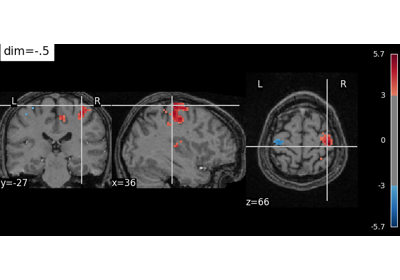

Fetch left vs right button press contrast maps from the localizer.

Examples using nilearn.datasets.fetch_localizer_button_task

Controlling the contrast of the background when plotting